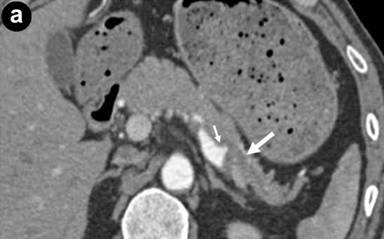

However, he was again admitted to our hospital because of epigastric pain and melena. On admission, he was hemodynamically stable. Physical examination revealed tenderness in the epigastrium. Laboratory data on admission showed mild anemia (hemoglobin 9.8 g/dL; reference range: 13.2-17.2 g/dL), an elevated white cell count (10,300 mm-3; reference range: 3,600-9,600 mm-3) and an elevated serum amylase level (1,246 U/L; reference range: 37-125 U/L). Contrast-enhanced computed tomography (CECT) demonstrated a large fusiform aneurysm (maximum diameter 10 mm) of the middle-distal splenic artery (Figure 1a), and dissection of the proximal splenic artery and celiac artery (Figure 1b). The false lumen of the dissected proximal splenic artery was partially thrombosed, and the true lumen was extremely narrow (Figure 1c). Mild enlargement of the pancreas was observed. However, no elevation of the fat density level around the pancreas was evident. There were no findings suggestive of chronic pancreatitis, such as pancreatic calcification, irregularity of the pancreatic duct and atrophy of the pancreas. CECT showed no signs of any pancreatic cyst or tumor. We made a tentative diagnosis of hemosuccus pancreaticus due to rupture of a splenic arterial aneurysm induced by acute pancreatitis.

Figure 1. a. Contrast-enhanced computed tomography (CECT) revealing a large fusiform aneurysm of the middle-distal splenic artery (arrow). b. Sagittal section of CECT showing dissection of the celiac artery (arrow). c. 3D-CT angiography showing dissection of the celiac artery (arrow head), narrowing of the proximal splenic artery (small arrow) and a fusiform aneurysm of the middle-distal splenic artery (large arrow). |